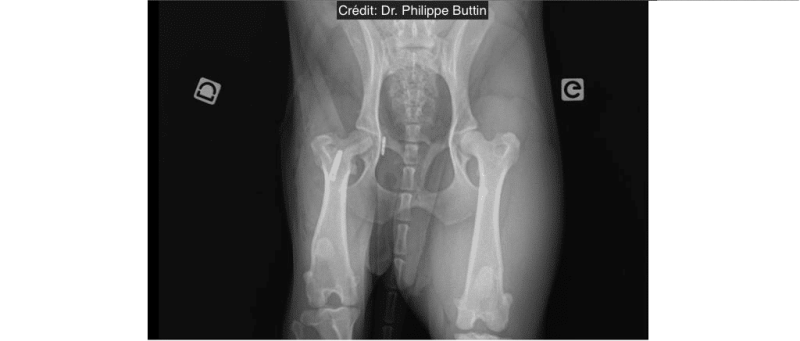

Extra-articular stabilization of craniodorsal hip dislocation

Extra-articular stabilization of caudo-ventral hip dislocation

Hip dislocation : Round ligament reconstruction

Radiologické snímky